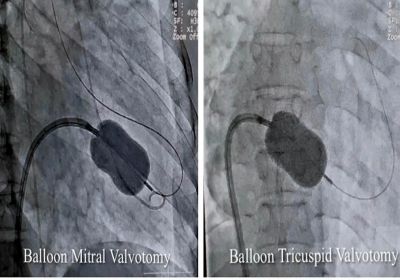

जबलपुर में विशेषज्ञों ने बैलून तकनीक से मिट्रल व ट्राइकसपिड वॉल्व की सिकुड़न का बिना सर्जरी के इलाज किया

2 Jan, 2025 02:58 PM IST | ASIAVARTANEWS.COMजबलपुर रयूमेटिक हृदय रोग से पीड़ित 40 वर्षीय महिला का मेडिकल कॉलेज के सुपर स्पेशलिटी अस्पताल...